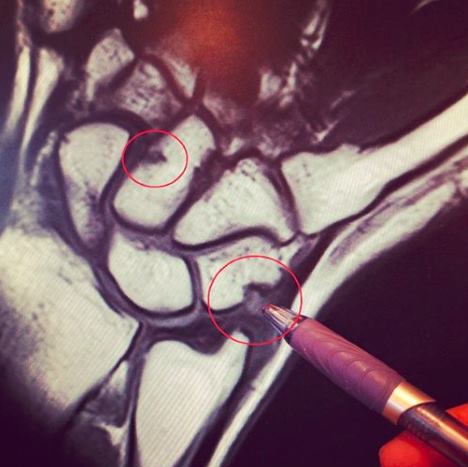

Marita Engzelius har nå fått undersøkt armen. Det viser seg at hun har hatt

skader i to av håndrotsbena i høyre hånd.

Marita

studerer MR-bildet av høyre hånd

Da jeg kom hjem til Norge, fikk jeg tatt MR. Jeg gjorde dette for å forsikre meg

om at jeg kun hadde en vanlig betennelse og ikke noe annet. Dessverre var ikke

dette tilfellet… Væskeansamling og hevelser inne i to av håndrotsbena i

håndleddet og i tillegg en kraftig senebetennelse. Jeg har blitt fortalt at

hadde jeg fortsatt å trene nå, hadde jeg dratt på meg et tretthetsbrudd.

Konklusjonen var at for å få de skadene jeg nå har pådratt meg, må jeg ha utsatt

håndleddet for en god del juling.